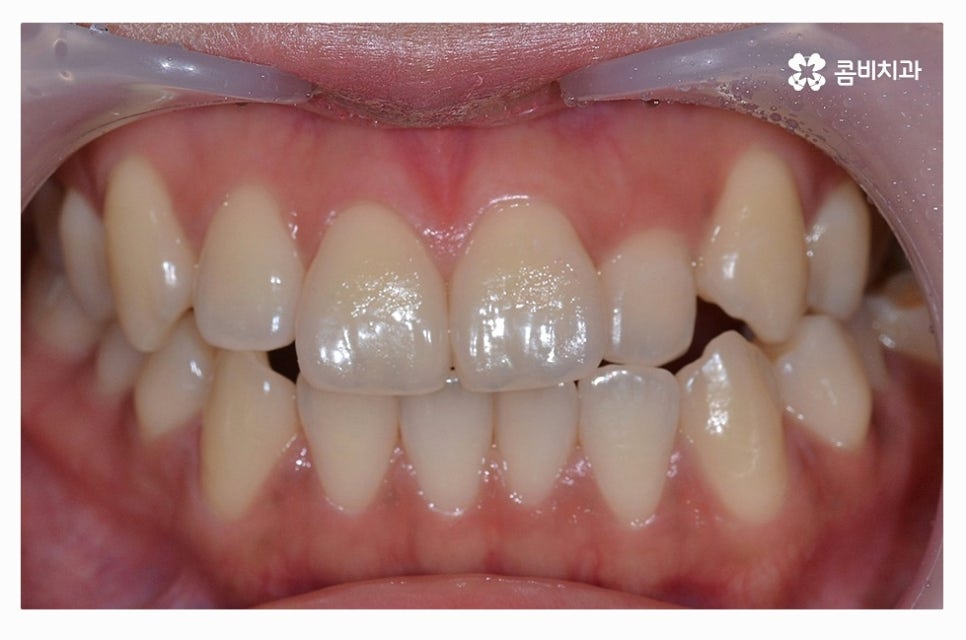

출처 아카이브 열기덧니의 이유는 다양하지만 일반적으로는 유치를 늦게 발치하거나

턱뼈가 좁은 경우, 치아 크기가 큰 경우, 습관

유전적 요인과 환경적인 요인으로 나눌 수 있는데요.

덧니를 방치하게 되면 구강관리의 어려움으로 잇몸이나 충치질환이

발생할 가능성이 상대적으로 높고, 치아의 기능적인 부분과

심미적인 부분을 고려했을 때 덧니교정을 하는 것이 필요할 수 있어요.

덧니의 형태는 개개인에 따라 다르지만 덧니로 인해

치석이나 음식물이 방치되기 쉽기 때문에 나이가 들수록

충치 및 잇몸병에 시달리게 되는 확률이 높아질 수 있어요.